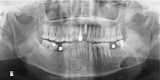

Stafne bone cavity (SBC) was mostly described as a small oval radiolucency in the posterior mandibular region. To the best of our knowledge, the literature does not contain any report of the use of cone beam CT (CBCT) sialography for the diagnosis of this entity. The aim of this paper is to present a large, irregular and expanded atypical SBC, which made diagnosis difficult. A CBCT sialography was performed to get a definite diagnosis of this rare entity.